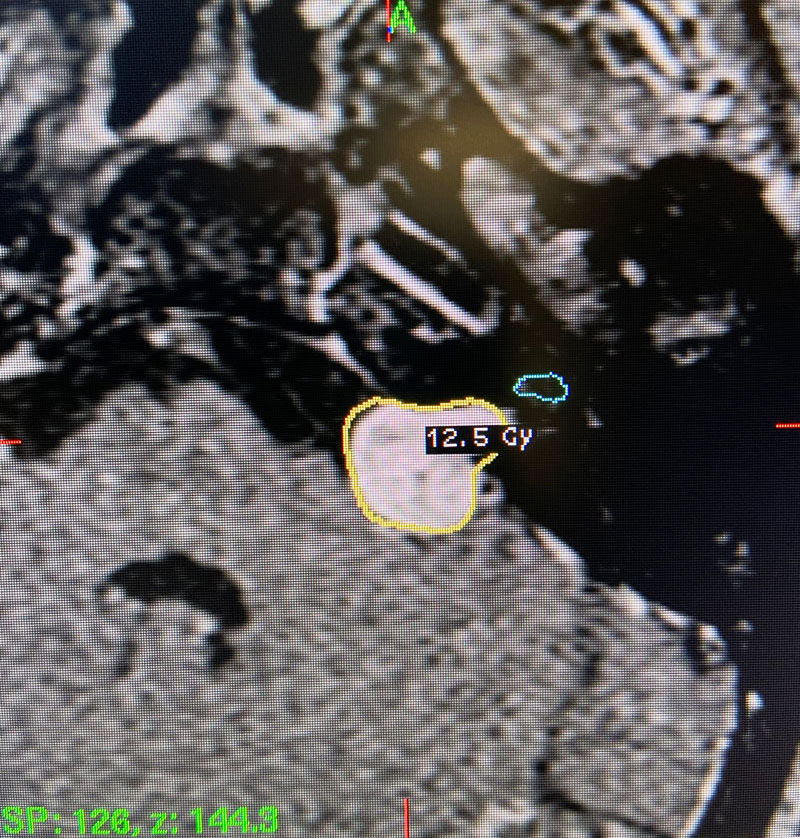

Image 1: Pre-operative imaging of the left acoustic neuroma.

Image 2: Intra-operative Gamma Knife treatment planning for the left acoustic neuroma. A tightly conformal treatment is set for 12.5Gy to the 50% isodose line. The cochlea has also been contoured, based off a fused image from a fine cut T2 sequence.

This patient: This patient had a moderate sized , symptomatic acoustic neuroma with serviceable hearing. Gamma Knife was recommended. A Gamma Knife treatment was performed by Dr. Michael Brisman. The radiation oncologist was Dr. Leester Wu. A treatment plan was made that was very conformal to the tumor. A prescription of 12.5Gy to the 50% isodose line was delivered. This plan involved a mean cochlear dose of 3.5Gy.

Technical Aspects of Gamma Knife Treatment: Dose to the tumor is set to 12-13 Gy to the edge of the tumor. The 50% isodose line is set to the edge of the tumor. Dosing under 12Gy is less effective at tumor control, and dosing over 13Gy puts the facial nerve at risk. There is evidence that the radiation dose to the cochlea affects whether hearing will ultimately be preserved. As such, if there is meaningful hearing at the time of treatment, the mean cochlear dose should be set to 4.2Gy or less. The cochlea is separately contoured at the time of treatment off fine cut T2 sequences which are then fused to the post contrast T1 images.